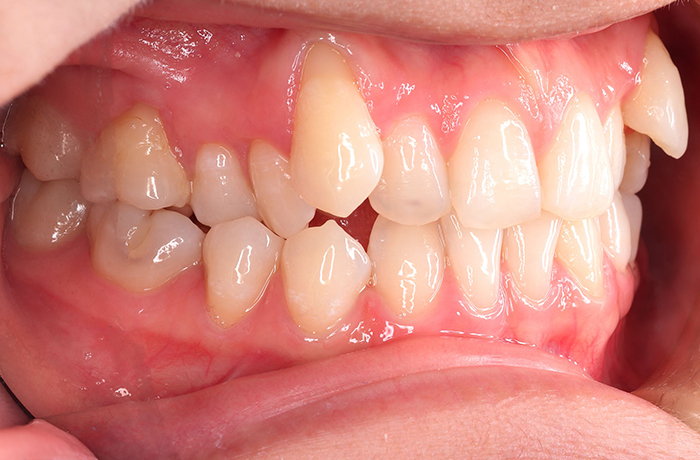

K様

治療前

年齢 27歳

性別 女性

治療名称 マウスピース型カスタムメイド矯正歯科装置(インビザライン)・コンプリヘンシブパッケージ(フルパッケージ)

総額治療費用 770,000円(税込10%) 金額備考 精密検査料・診断料 33,000円(税込10%)

治療期間 1年11か月 通院頻度など 40日ごと

1枚につき10日装着を指示しました。

治療内容

患者の症状 上顎前歯の前突、八重歯

治療方法 上下左右の第一小臼歯抜歯で、マウスピース型カスタムメイド矯正歯科装置による矯正

治療結果 上顎前歯の前突、八重歯が改善されました。

歯並びをより良くするために追加でアライナーを発注しました。

リスク/副作用 決められた時間装着する必要があります。